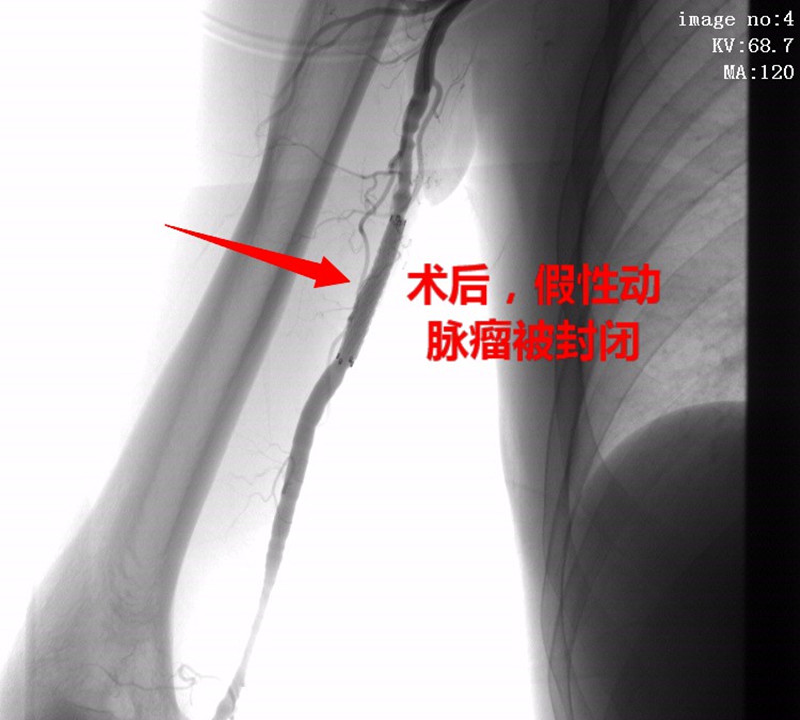

经我院外周介入科积极完善术前准备,于3月12日在DSA下为该患者行“右侧颈内动脉造影、右上肢动脉造影+右肱动脉假性动脉瘤覆膜支架腔内隔绝术”。术后查体:右侧肱骨中段触及包块,搏动性消失,听诊无杂音,包块缩小。

术后